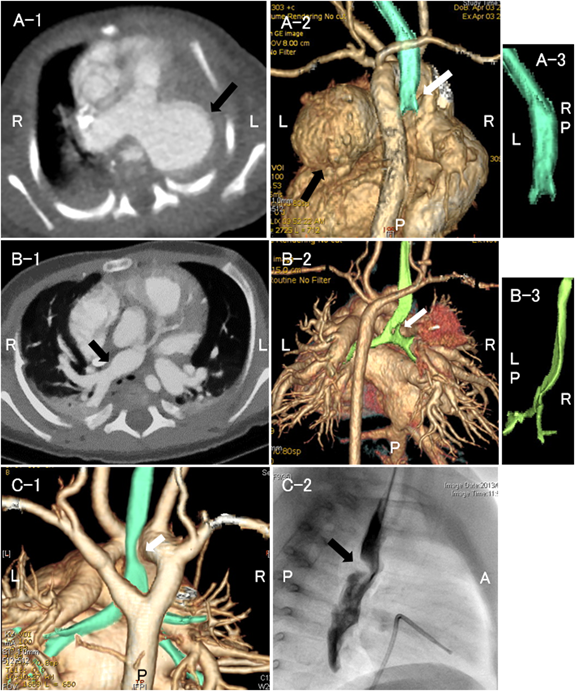

症例4以外の全例に造影CTを行い,心血管構造による気管気管支の圧排,扁平化を認めたため,外的圧迫による二次性気管気管支軟化症と診断した.先天性気管狭窄の症例はなかった.各群の代表的な画像をFig. 1に例示した.I群は主に拡大した肺動脈,II群は拡大した肺動脈や左房,III群は血管輪を形成する大動脈弓や動脈管索等で気管気管支を圧排されていた.症例14は右大動脈弓,Kommerell憩室を伴う左鎖骨下動脈起始異常で血管輪を形成し,左主気管支が主に圧排されていた(Fig. 2A).症例15は右大動脈弓,Kommerell憩室を伴う左腕頭動脈起始異常で非常に稀な血管奇形であった8).造影CTおよび心臓手術の術中所見で左総頸動脈・左鎖骨下動脈と上行大動脈との連続性がなかったことから確定診断した(Fig. 2B).

Fig. 2 Computed tomographic images of (A) Case 14 and (B) Case 15

A: The tracheal bifurcation (white arrow) and left main bronchus are compressed by the diverticulum of Kommerell (black arrow). B: The trachea and right main bronchus are compressed (black arrow). The left brachiocephalic artery (white arrows) arises from the descending aorta, coursing behind the esophagus toward the left. The vascular ring was relieved with division of the arterial ligament.